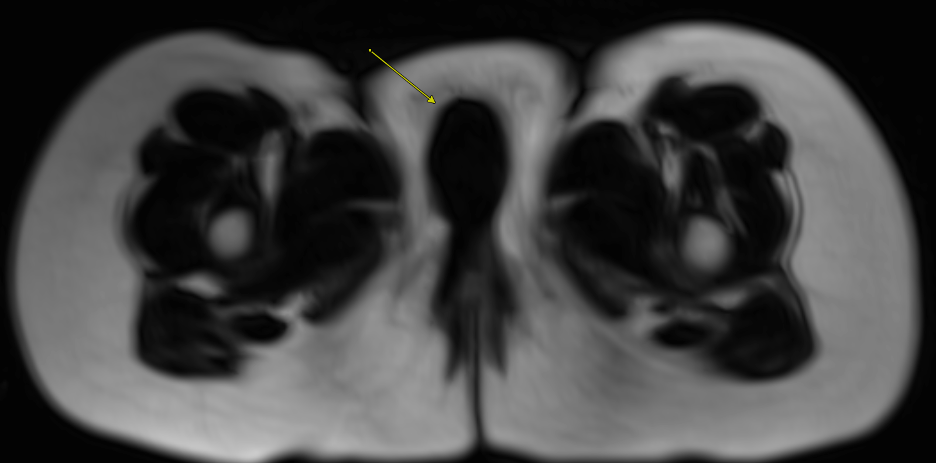

Diagnostic and laboratory testing. Contrast-enhanced MRI of the pelvis was obtained for better lesion characterization and surgical planning. MRI demonstrated a well-circumscribed, predominantly solid lesion with some cystic components, measuring 2.8 x 2.0 x 2.6 cm in the right labial region. The mass was homogenously hypointense on T1-weighted images and intermediate intensity T2-weighted images (Figure 1). Post-contrast imaging revealed heterogeneous, predominantly peripheral enhancement (Figure 2). Diffusion-weighted imaging (DWI) suggested high cellularity with diffuse diffusion restriction (Figure 3). T1 imaging suggested the absence of microscopic fat, hemorrhage, or calcifications (Figures 1 and 4). It appeared confined to the labia without deep pelvic infiltration. There were no suspicious satellite lesions or lymphadenopathy in imaging.

Figure 4. Axial diffusion-weighted imaging (DWI; left) and apparent diffusion coefficient (ADC; right) images show diffusion restriction within the mass (arrow). This finding suggests high cellularity and raises concern for malignancy.